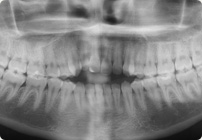

Caso: 11 años

Adolescente: Clase II

Mordida Cruzada Posterior

Sin extracción

Sin uso de expansores

6 alambres superiores

5 alambres inferiores

Sin uso de elásticos

Retenedores: Interior Fijo de TMA y Hawley en superior

Tiempo de tratamiento: 14 Visitas